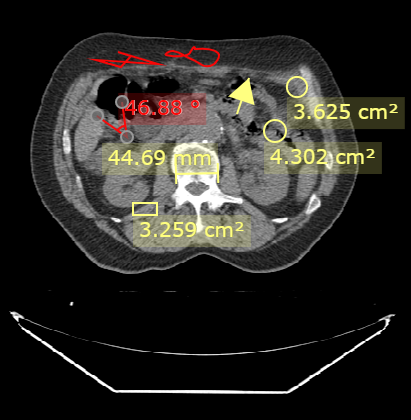

在使用测量与绘制时,DcmViewer默认颜色为黄色。

DcmViewer 基于 Konvajs Shapes 的基础图形开发,并提供以下的测量工具。

点亮按钮,在图像上拖动图标,即可画出所选按钮的形状及测量数据。 再次点击该按钮,取消点亮来取消绘制测量。

选中所画出的的形状,可以通过拖动来改变形状的大小及位置来调整测量。